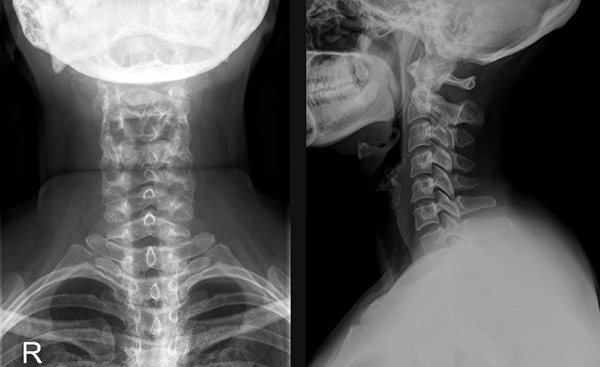

Отложение солей в шейном отделе (как убрать будет описано далее в статье) должно быть определено специалистом после обследований, которые включают 2 шага:

- Лабораторные, предполагающие сдачу анализов крови и мочи. Исследования крови направлено на выявление уровня лейкоцитов и мочевой кислоты, по анализу мочи определяется уровень кислотности и также содержание мочевой кислоты.

- Рентгенография шейного отдела.

Пораженная область может быть дополнительно исследована с помощью УЗИ, МРТ или КТ. В процессе установления диагноза пациенту потребуется консультация ортопеда, ревматолога и невролога.